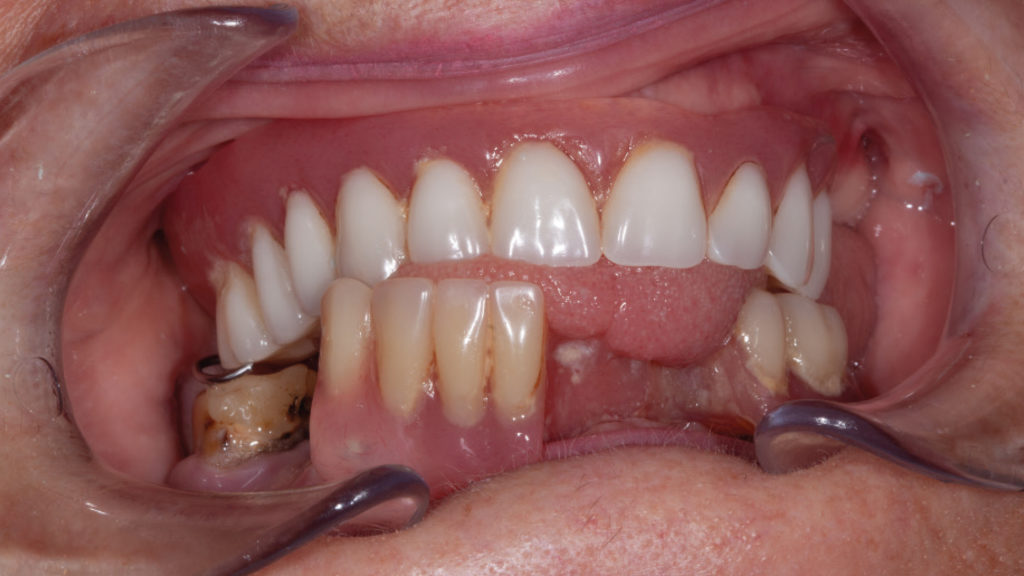

Eine 58-jährige Patientin wurde in der Praxis vorstellig, da sie mit ihrer momentanen Versorgung funktionell und ästhetisch unzufrieden war (Abb. 1). Beim Kauen schaukelte die Teilprothese im Unterkiefer und die Totalprothese im Oberkiefer, sodass sie keinen sicheren Halt boten. Die Konfektionszähne wirkten leblos, die mukogingivalen Anteile waren glatt und eben gestaltet und wirkten künstlich. Nach Extraktionen im Unterkiefer war regio 31 bis 34 unversorgt, da die Teilprothese nicht erweitert worden war. Lediglich Zahn 46 war noch vorhanden, den die Patientin auf jeden Fall behalten wollte. Der Molar erwies sich als erhaltungswürdig und zeigte klinisch und röntgenologisch keine Anzeichen für eine starke parodontale Schädigung. Nachdem der Patientin die Auswirkung einer Teilprothese auf den einzigen verbliebenen Zahn 46 erklärt worden war, wurde entschieden, die neue Prothese im Unterkiefer so zu gestalten, dass diese bei einem Zahnverlust durch minimale Veränderung des Prothesendesigns mit einem Konfektionszahn ergänzt werden konnte.